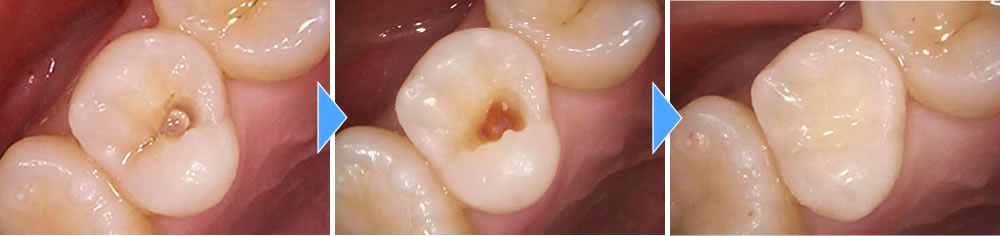

2次カリエスを治療後にセラミックインレーで修復した症例

年齢

20代

性別

女性